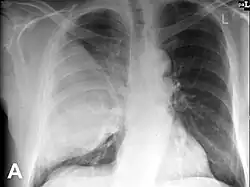

Hamartoma, błędniak[1] (łac. hamartoma, z gr. ἁμαρτία, hamartia = błąd, ang. hamartoma) – guz o charakterze nienowotworowym, będący zaburzeniem rozwojowym. Hamartoma zbudowane jest z dojrzałych tkanek normalnie występujących w danym narządzie, ale chaotycznie rozmieszczonych w guzie, nierzadko w zaburzonych proporcjach ilościowych. Hamartomata występują w różnych narządach – często są rozpoznawane w płucach (hamartoma pulmonis), na zdjęciach przeglądowych klatki piersiowej dają obraz cienia okrągłego – tam jednak jest to nazwa mieszanego nowotworu łagodnego[2]; hamartoma podwzgórza (hamartoma hypothalami) może być objawowy, wywierając ucisk na sąsiadujące struktury mózgowia i zaburzając ich czynność. Guzy te mogą stanowić część obrazu klinicznego zespołów wad wrodzonych, np. liczne hamartomata są charakterystyczne dla zespołu Cowden i stwardnienia guzowatego. Stan, w którym występują liczne hamartomata, określa się jako hamartomatosis.